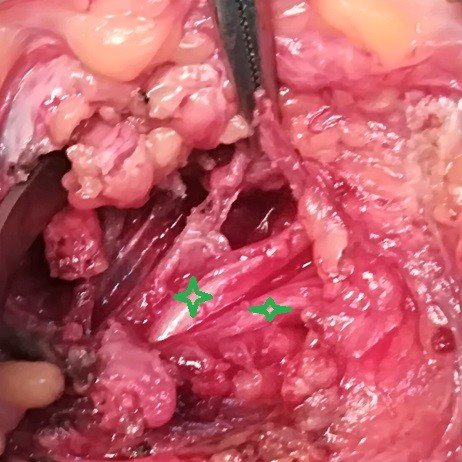

Live images during surgery showing the location of the tumor and determining the location of the surgical incision to explore the tumor. Then it was completely removed and the nerve plexus was completely freed without any damage to the nerves. After the surgery, the patient recovered well and is leading a normal life.

A successful precise surgery was performed to remove a tumor from the right cervical plexus. The cervical plexus is a complex network of nerves in the neck area that controls movement and sensation in the shoulder, arm, and hand.